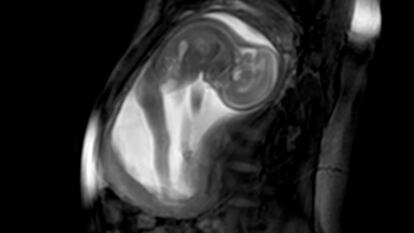

Lo dicen las conclusiones de un estudio del Imperial College de Londres, publicado en enero por la Royal Society: los fetos patean y se mueven para ejercitar los músculos y formar bien las articulaciones y los huesos. Este tipo de movimientos aportan al bebé beneficios similares a los que obtenemos los adultos cuando practicamos algún deporte: ganar músculo y fortalecer los huesos.

Los bebés empiezan a mover la cabeza en torno a la décima semana de embarazo, las patadas tardan un poco más en llegar. Es entre las semanas 16 y 18 cuando las futuras madres empiezan a sentir los golpes en su tripa y las que más potencia tienen son entre las 20 y 30 semanas. En este periodo tienen una fuerza de 45 newtons, el equivalente a la presión que ejercería sobre el suelo una garrafa de algo más de 4 kilos y medio.